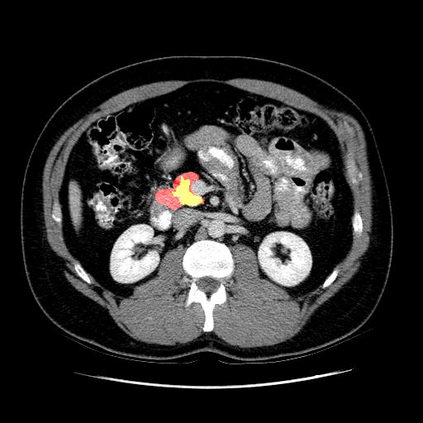

In this paper, we adopt 3D Convolutional Neural Networks to segment volumetric medical images. Although deep neural networks have been proven to be very effective on many 2D vision tasks, it is still challenging to apply them to 3D tasks due to the limited amount of annotated 3D data and limited computational resources. We propose a novel 3D-based coarse-to-fine framework to effectively and efficiently tackle these challenges. The proposed 3D-based framework outperforms the 2D counterpart to a large margin since it can leverage the rich spatial infor- mation along all three axes. We conduct experiments on two datasets which include healthy and pathological pancreases respectively, and achieve the current state-of-the-art in terms of Dice-S{\o}rensen Coefficient (DSC). On the NIH pancreas segmentation dataset, we outperform the previous best by an average of over 2%, and the worst case is improved by 7% to reach almost 70%, which indicates the reliability of our framework in clinical applications.